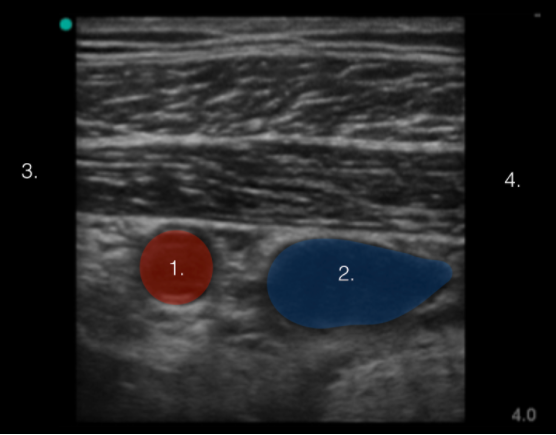

Axillary Artery and Vein Image

Axillary Artery

Axillary Vein

Cranial and Lateral

Caudal and Medial